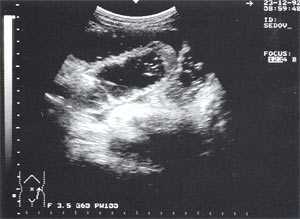

Свободная жидкость в брюшной полости - отмечена в 18% случаев (рис. 4), из них 80% у мужчин и 20% у женщин. Жидкость в объеме до 100 мл определяется только в одной анатомической области ( чаще в малом тазу), более 100 мл - по боковым каналам и в других отделах брюшной полости. В первые дни развития острого панкреатита жидкость гомогенная, после 6-12 сут. часто структура неоднородная из-за "нитевидных" включений (как правило, фибрин).

Рис. 4. Расширенные петли тонкого кишечника до 3,5 см, заполненные жидким содержимым на фоне свободной жидкости в брюшной полости.